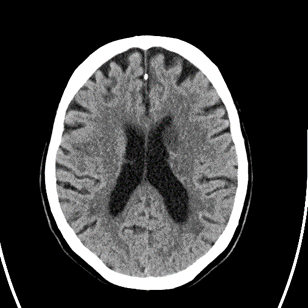

3/ On arrival, NIHSS now 3 for R drift, ๐Ÿ˜•, no aphasia. #CTP as below. CT still with #ASPECTS 9:

4/ How do you manage the patient?